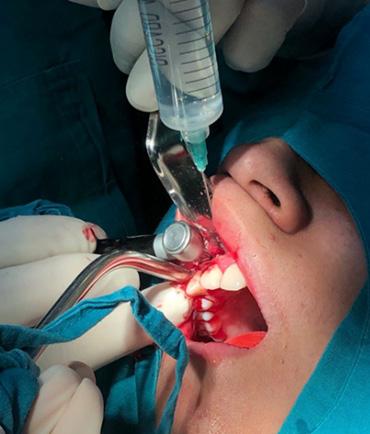

Durante el estudio, la cabeza de cada estudiante fue posicionada en relación al plano de Frankfurt (paralelo al piso), mismo que se logró con una regla nivel de 30 cm; dicho plano anatómico se extiende desde el agujero infraorbitario a la parte media del borde superior del conducto auditivo externo (12), estos reparos anatómicos se identificaron en el estudiante mediante la palpación digital del borde inferior de la órbita y a simple vista del trago del pabellón auricular (figura 1).

Quelca-Portugal-Yujra-Chuquimia

Seguidamente y mediante palpación se localizó de forma bilateral el ángulo mandibular, el reborde orbitario lateral y la arteria facial de cada estudiante, ésta última estructura se identificó a nivel del borde inferior del maxilar inferior, percibiendo sus pulsaciones con facilidad. Con un lápiz dermográfico se marcó un punto en la piel donde se localizó a estas tres estructuras. Desde el punto marcado que representaba a la arteria facial, se trazó una línea vertical y ascendente hasta la referencia anatómica más relevante, identificable y no modificable por procesos infecciosos submandibulares (arco cigomático). Finalmente se determinó la distancia entre el borde lateral de la órbita y la proyección vertical ascendente de la arteria facial sobre el arco cigomático (figura 1).

Fuente: Elaboración propia, julio 2019

Figura 1. Puntos y líneas utilizadas para la localización de referencia anatómica no modificable sobre la base de la arteria facial. Localización de referencia anatómica inmodificable sobre la base de la arteria facial en infecciones submandibulares odontogénicas